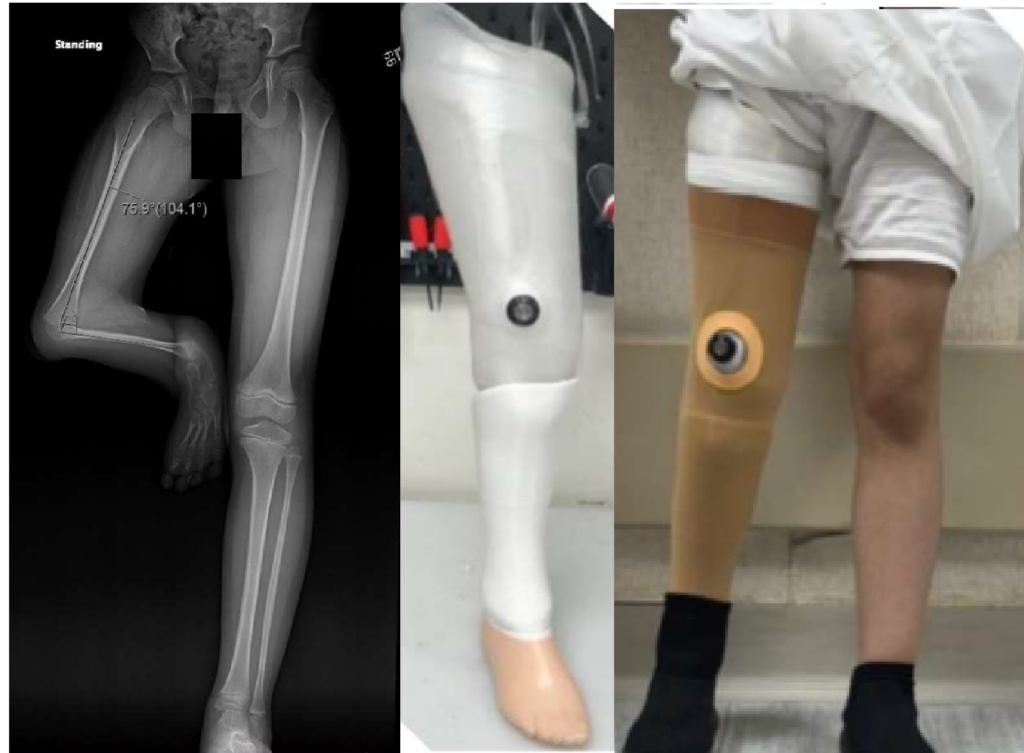

After losing his leg in a tragic accident, Badsha found himself grappling with feelings of despair and hopelessness, believing that his dreams had been shattered. However, his journey toward recovery began when he received a state-of-the-art prosthetic limb from PIRS, a life-changing gift made possible through the unwavering commitment and generosity of CHEF International.